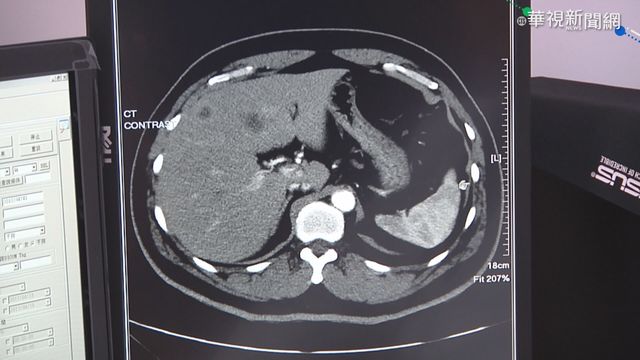

根據衛福部2017年公佈的資料,大腸癌連續12年,癌症排名第一,很多名人都死於大腸癌,像是豬哥亮,這當然跟飲食習慣有很大的關係,而大腸癌又被封為隱形殺手,是因爲罹患的初期,幾乎不會有任何的症狀,對此醫生呼籲,建議三十歲以上的民眾,至少做1次大腸鏡檢查,早期發現治療,飲食方面少吃加工肉品含糖飲料、均衡飲食、作息正常,才是健康得不二法門。

大口吃漢堡炸雞,喝飲料好紓壓,但是不健康的飲食,卻有可能導致大腸癌找上你,根據衛福部2017年公佈的資料,大腸癌連續12年排名第一,死亡率排名第三名,更可怕的是又被封為隱型殺手。

臨床上常常聽到說,大便習慣改變或大便出血,有時候他真的是腫瘤,而且他已經屬於期數比較高了,國泰健康管理預防醫學部部長陳皇光:「大概有70%都沒有什麼臨床症狀,一般臨床上常常聽到說,大便習慣改變或大便出血,有時候它真的是腫瘤,而且它已經屬於期數比較高了。」

早期沒症狀,那就只能靠定期篩檢,醫生認為現在最主要檢測大腸癌的檢查方法,除了糞便潛血就是大腸鏡,建議若檢查完沒有瘜肉家族病史,每三年安排一次檢查,當然飲食也要改變,營養師王盈堤:「全穀根莖類可以取代一些精緻澱粉,那第二個部分的話,其實我們在肉類的選擇上面,就是盡量要避免完全以紅肉為主。」